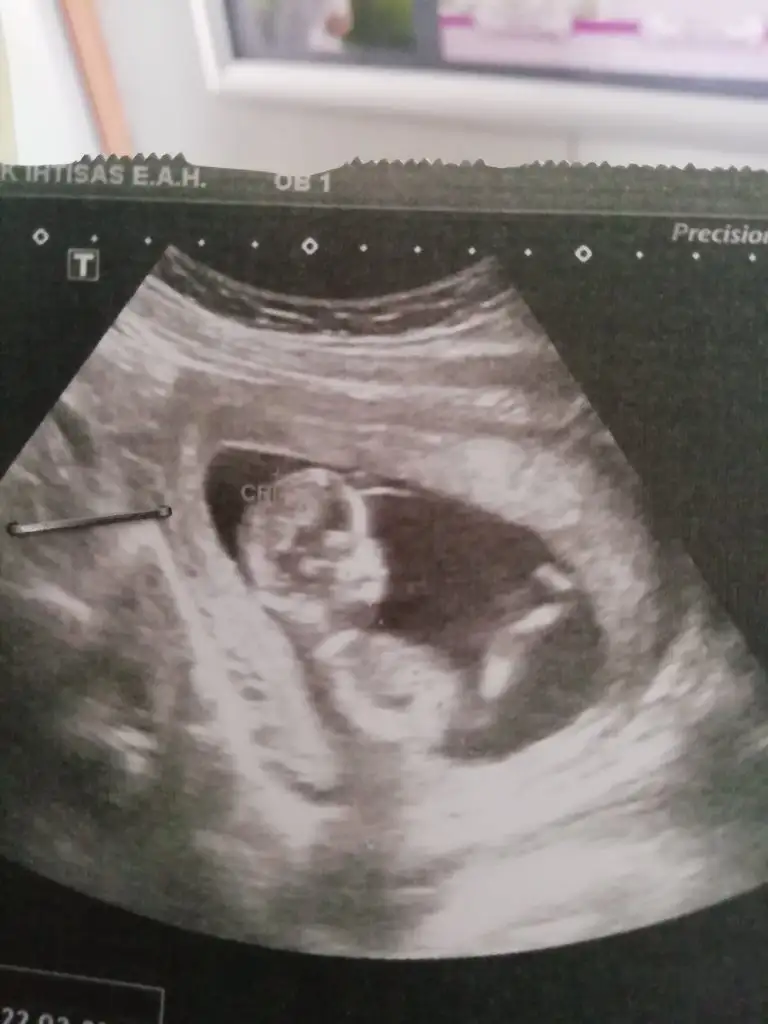

dr soylemeden siz gorun genital nub teorisi ( bebegin cinsiyeti)